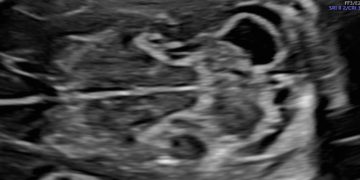

Casi del Mese di Marzo 2023

Cari soci, finalmente online le soluzioni dei casi per il mese di Marzo!!! Grazie a Ilaria Fantasia e Gabriele Saccone!! Caso 1 [pdf-embedder url="https://www.sieog.it/wp-content/uploads/2023/03/caso-clinico-Fantasia-risposta-marzo-2023.pdf" title="caso...